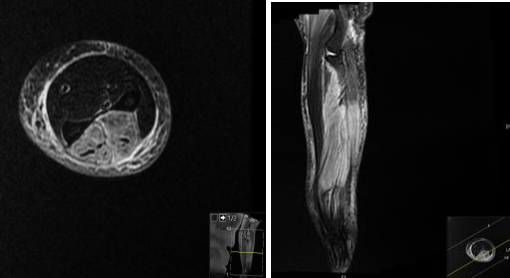

MRI Forearm Lt (non-contrast) report:

The muscles within the posterior compartment of the forearm, including the extensor muscles, are diffusely enlarged and demonstrate increased signal intensity on T2-weighted sequences with anterior bowing of the deep fascia. No obvious internal collections to suggest abscess formation.

Note is also made of extensive subcutaneous oedema. The oedema extends from the wrist to the elbow, involving the soft tissues and the muscles of the forearm. There is no evidence of any underlying bony or joint abnormalities.

The flexor muscles within the anterior compartment of the forearm are within normal limits with no evidence of injury or oedema.

The tendons and ligaments are intact, with no evidence of tearing or avulsion.

Photo 1 : Axial STIR Left Forearm          Photo 2 : Cor STIR  Left Forearm

Photo 3: Cor T1 Left Forearm                  Photo 4: Axial T2 PR Left Forearm

Conclusion of MRI:

Diffuse thickening an oedema change involving the muscles of the posterior compartment and the subcutaneous oedema. Given the patient's history of antiphospholipid syndrome and recent trauma followed by severe pain, the MRI findings could be in keeping with suspected compartment syndrome, this needs urgent surgical review.